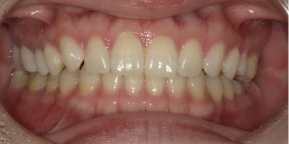

29歳女性のビフォーアフター

| 診断 | 叢生(デコボコがある状態)、過蓋咬合 |

|---|---|

| 治療方針 | インビザラインシステムにて主にIPR(歯と歯の間をわずかに削合してスペースを獲得する方法)を組み込んだ動的矯正治療を行い、叢生を改善後、保定を行う。臼歯部の咬合関係はプランの関係上維持して叢生と前歯部の咬合改善を目指した。 |

| 治療費 ※ | 60万4千円(診断、型取り、PMTC、保定装置を含む料金) |

| 治療期間 | 1年5か月 |

| リスク | 1日20時間以上マウスピースを使用できない場合、歯が動かない可能性がある。装着時や食事時に痛みを伴う。歯肉退縮や虫歯になるおそれがある。また、指導通りに装着できていない場合や適切なブラッシングが出来ていないとそのリスクが高くなる。歯根が短くなることがある。ごくまれに歯の神経が損傷してしまうことがある。過去にぶつけたり深い虫歯治療をしたことがあるとそのリスクはやや高くなる。矯正後には保定装置が必要。適切な使用ができない場合、後戻りの原因となる。将来的に歯並びが動いて再矯正が必要な場合がある。親知らずが正常に生えていない場合、その可能性がやや高くなる。 |

※ 治療費は、治療当時の費用で、現在の費用と異なる可能性があります。現在の費用は治療費のページでご確認くださいませ。